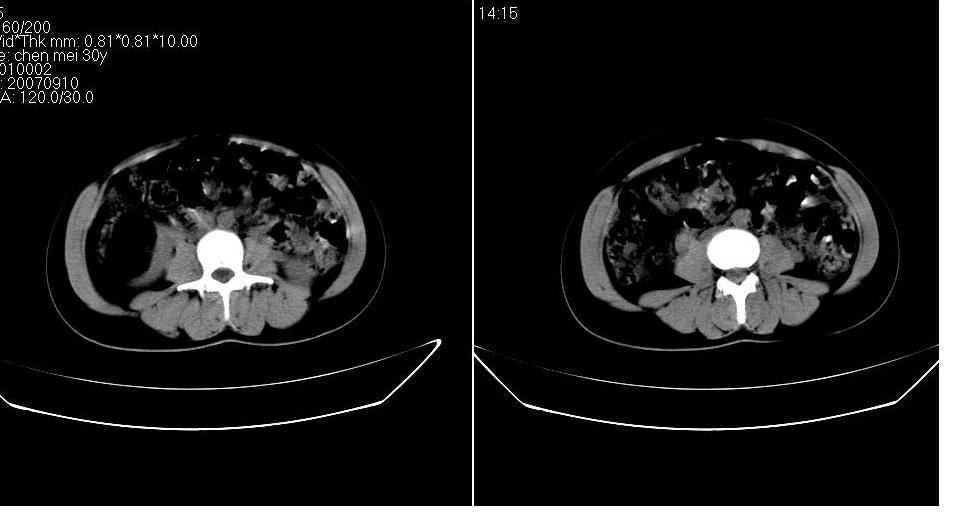

以下是引用求知若渴在2007-9-10 20:08:00的发言:[br]病变以脂肪成分为主,应该是错构瘤。另肝内胆管结石

以下是引用xulianj在2007-9-10 20:51:00的发言:[br]错构瘤,支持。含脂肪成分较多,证明较为成熟。

以下是引用王仕学在2007-9-10 21:34:00的发言:[br]有脂肪密度,哪怕是一点点,首先考虑错构瘤。还是增强吧,好说些!